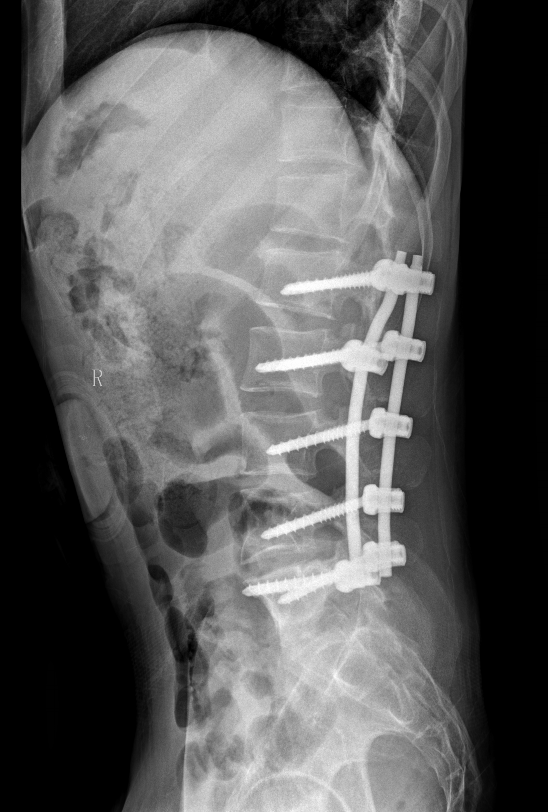

术前影像资料提示:患者左侧腹膜后存在一巨大恶性神经鞘瘤,最大径达20.1厘米。肿瘤已广泛侵犯周围结构,包括同侧髂骨、腰椎以及输尿管。

术后X线